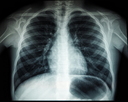

“오늘 엑스레이 찍으실게요”…무심코 선 ‘차가운 판때기’ 0.02~0.1mSv의 진실